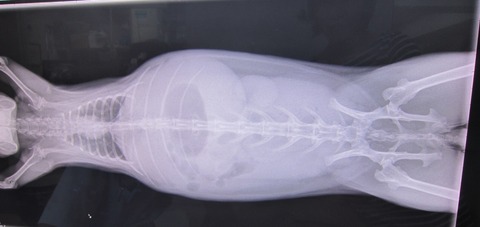

9日の譲渡会、

とてもよく食べ、なでなでアピール頑張ってたかぐらちゃん

排泄物もお見事でした

最中は上の画像の通りの排泄物に、たくさんナデナデして頂き、

帰宅、すぐのご飯も完食したのち、第2ご飯の催促もご覧の通りで…

心配なし、問題なし、